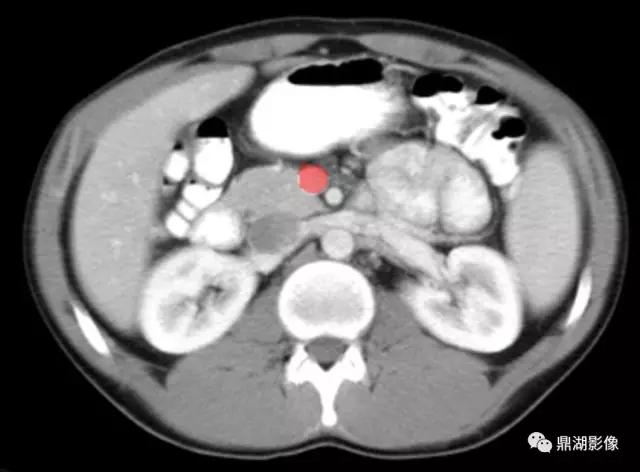

肠系膜上动脉(Superior Mesenteric Artery)

肠系膜上静脉(Superior Mesenteric Vein)